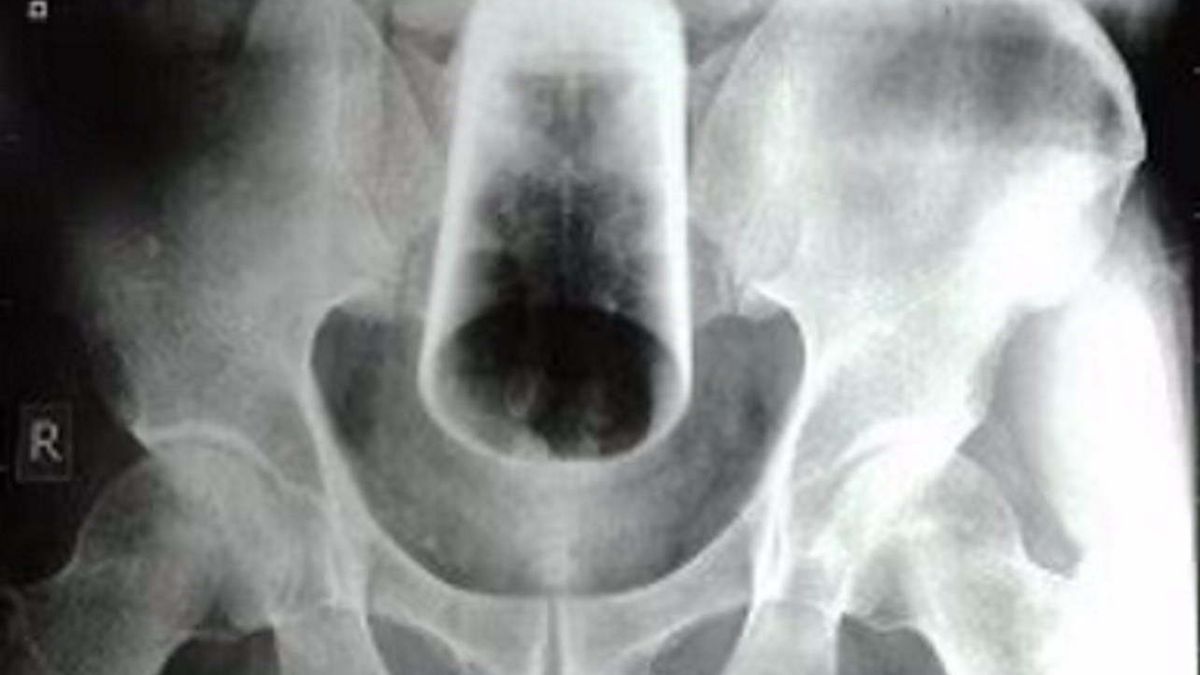

Lekarze obawiali się, że w trakcie zabiegu dojdzie do uszkodzenia jelita przez szkło

Lekarze obawiali się, że w trakcie zabiegu dojdzie do uszkodzenia jelita przez szkło © "Journal of the Nepal Medical Association"

Lekarze musieli zmierzyć się z trudnym zadaniem. Próby przeprowadzenia sigmoidoskopii, a także ręcznego usunięcia szklanego przedmiotu przez odbyt nie przyniosły rezultatu. Medycy odstąpili od obu procedur z uwagi na duże ryzyko pęknięcia szklanki, a co za tym idzie zagrożenia uszkodzeniem ściany jelita lub zwieracza odbytu. Wszystko dlatego, że "szklanka znajdowała się wysoko, była odwrócona i ciasno zaklinowana".

Konieczne było nacięcie jelita – enterotomia esicy – które umożliwiło bezpieczne usunięcie ciała obcego z przewodu pokarmowego Nepalczyka. Zabieg zakończył się sukcesem, a w trzeciej dobie u chorego ustąpiły dolegliwości pod postacią bólu brzucha i wzdęć. W szóstej dobie u pacjenta ustąpiły zaparcia, a po siedmiu dniach hospitalizacji pacjent został wypisany do domu.